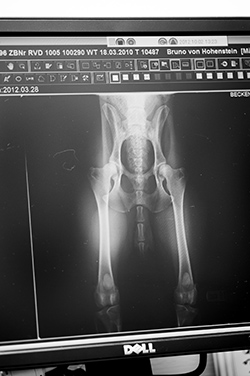

Digitale Röntgen-Diagnostik

- Allgemeine Röntgendiagnostik

- Zuchtzulassung zur Untersuchung auf Hüftgelenkdysplasie/

Ellenbogendysplasie (HD / ED) - Zuchtzulassungsuntersuchung auf Patellaluxation